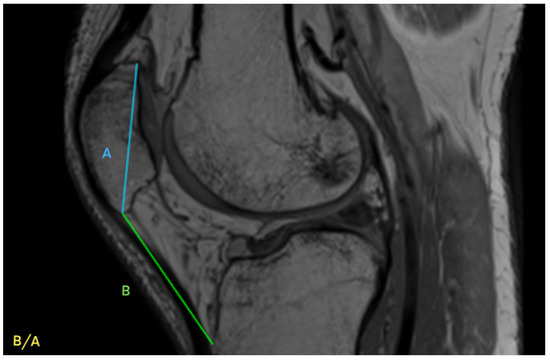

| IS | Insall–Salvati ratio |

- Insall, J.; Salvati, E. Patella Position in the Normal Knee Joint. Radiology 1971, 101, 101–104. [Google Scholar] [CrossRef]